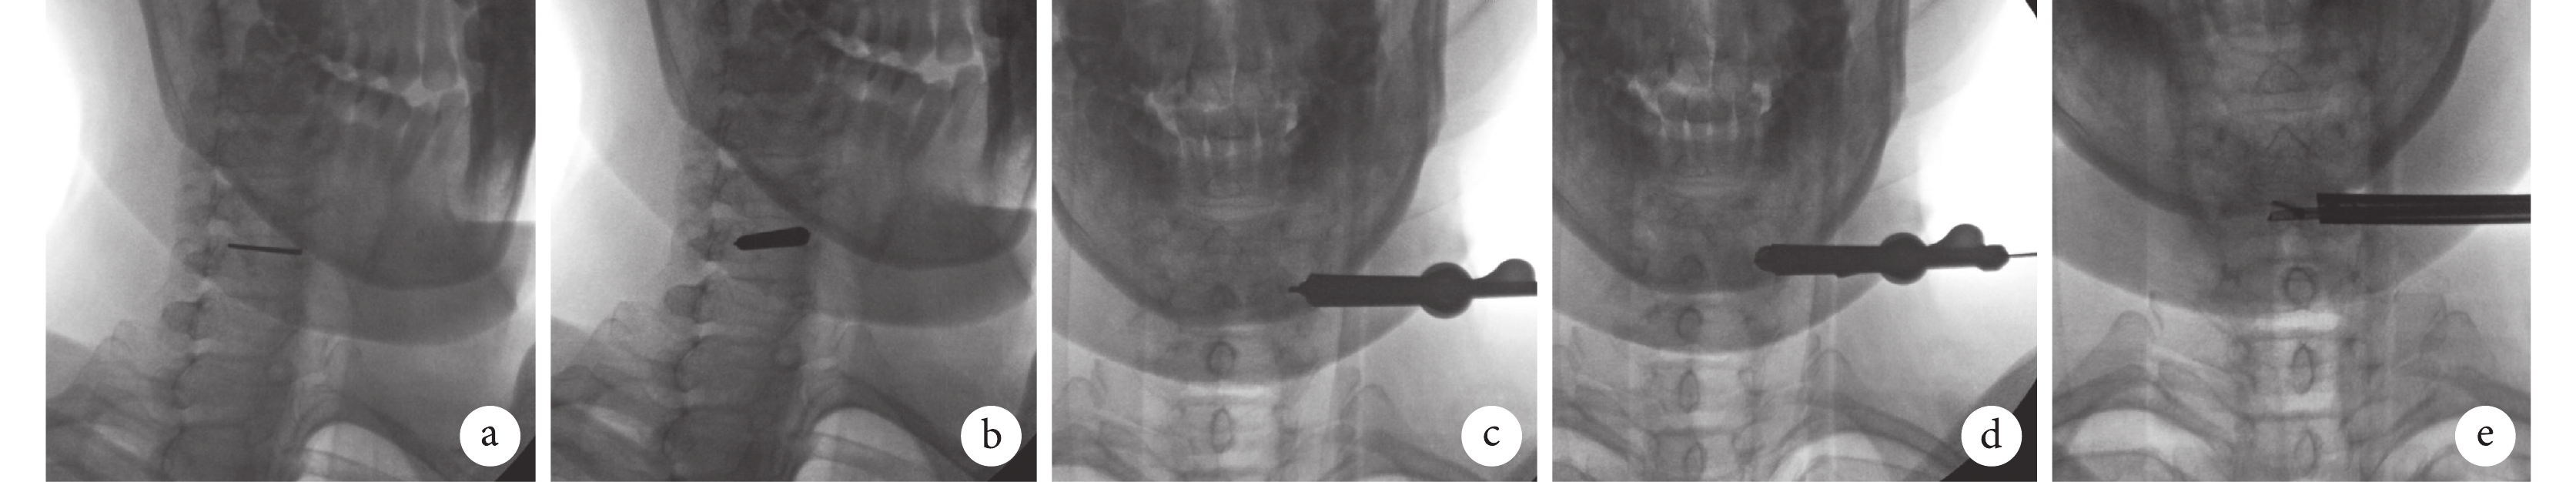

a. 克氏針錨定于下位頸椎側塊在椎弓根表面投影點;b. 沿克氏針置入導桿;c. 沿克氏針及導桿置入鏡鞘;d. 沿導桿置入環鋸并順時針旋轉,于側塊表面作一骨面環形定位;e. 磨鉆到達椎體中份,確認髓核鉗位置

Figure1. The vertical anchor technique and insertion of percutaneous endoscopic systema. Kirschner wire was anchored at the midline of the lateral mass of the lower cervical vertebrae; b. Inserted the dilator along the Kirschner wire; c. Inserted the working sheath along the dilator and Kirschner wire; d. Inserted the trephine along the dilator and rotated it clockwise to curve the surface of cortices; e. The location of endoscopic nuclear forceps was confirmed at the midline of vertebrae